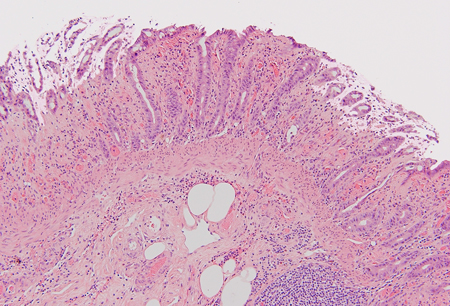

colite isquêmica

isquemia colônica não aguda